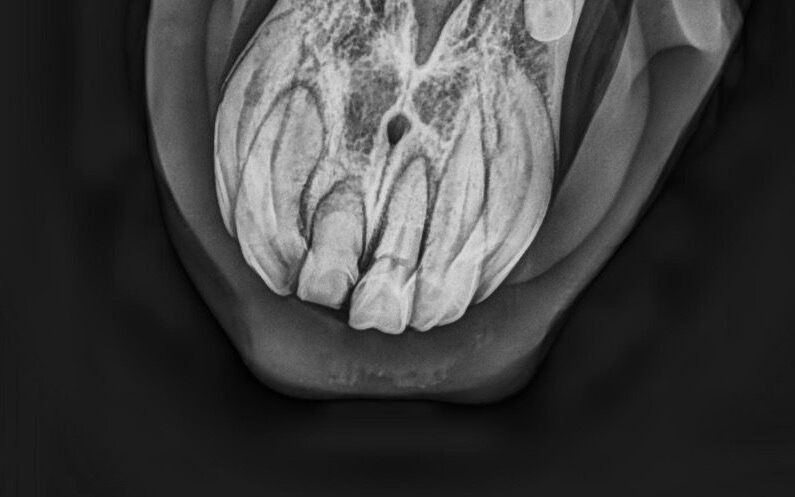

- röntgenologische Untersuchung zur Bestätigung der Verdachtsdiagnose EOTRH

- deutliche Befunde erkennbar

- resorptive und hyperzementotische Veränderungen an den Schneidezähnen/Schneidezahnwurzeln